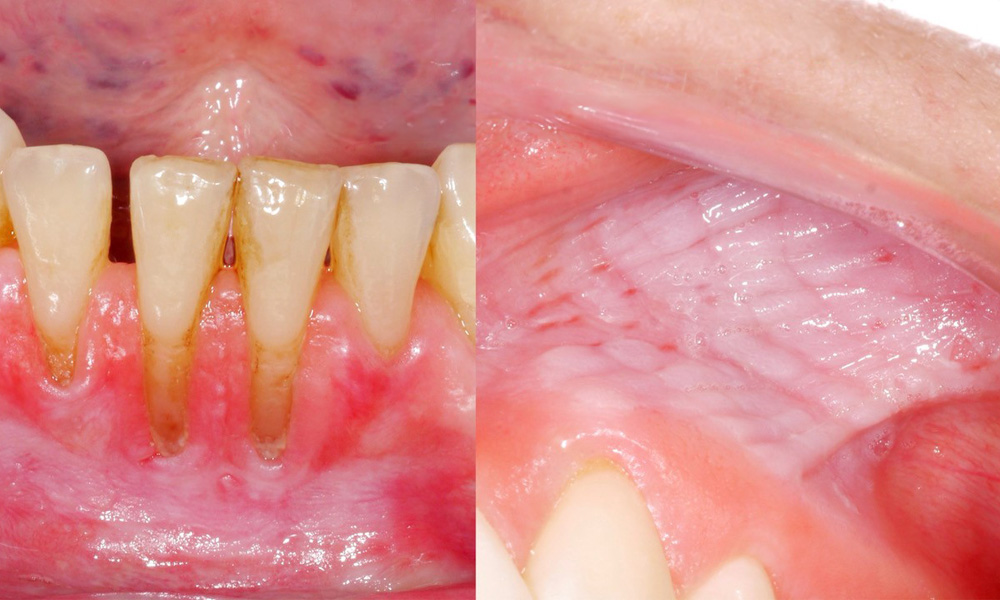

Снусът причинява лезии на лигавицата и гингивални рецесии

Клиничното изследване показа, че редовната консумация на снус може да има следните ефекти върху лигавицата на устната кухина:

- Приблизително 80% от изследваните лица, които са консумирали снус ежедневно, са показали лезии на лигавицата, предизвикани от него.

- Приблизително 20% от изследваните лица, които са консумирали снус ежедневно, са имали индуцирана гингивална рецесия.